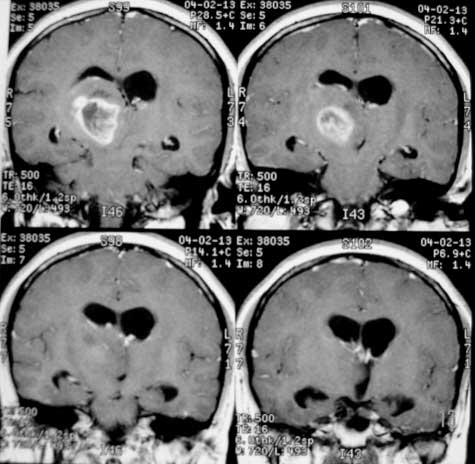

女性,28岁。头痛请会诊

右侧丘脑类圆形等t1,长t2病灶,t1增强明显强化。

女性,28岁。头痛请会诊。

考虑:①丘脑胶质瘤可能大。②脑积水。

t1等信号内出现点状高信号,考虑为出血灶,肿块内侧可见弧形低信号,为脑积液影。长t2,其内有混杂信号,周壁强化明显,内不规则强化,生长位置似在右侧丘脑,又似在来源于侧脑室,故脉络丛乳头状瘤不排外。

右侧丘脑胶质母细胞瘤可能

胶质瘤可能性大,请结合病史排除结核瘤的可能。